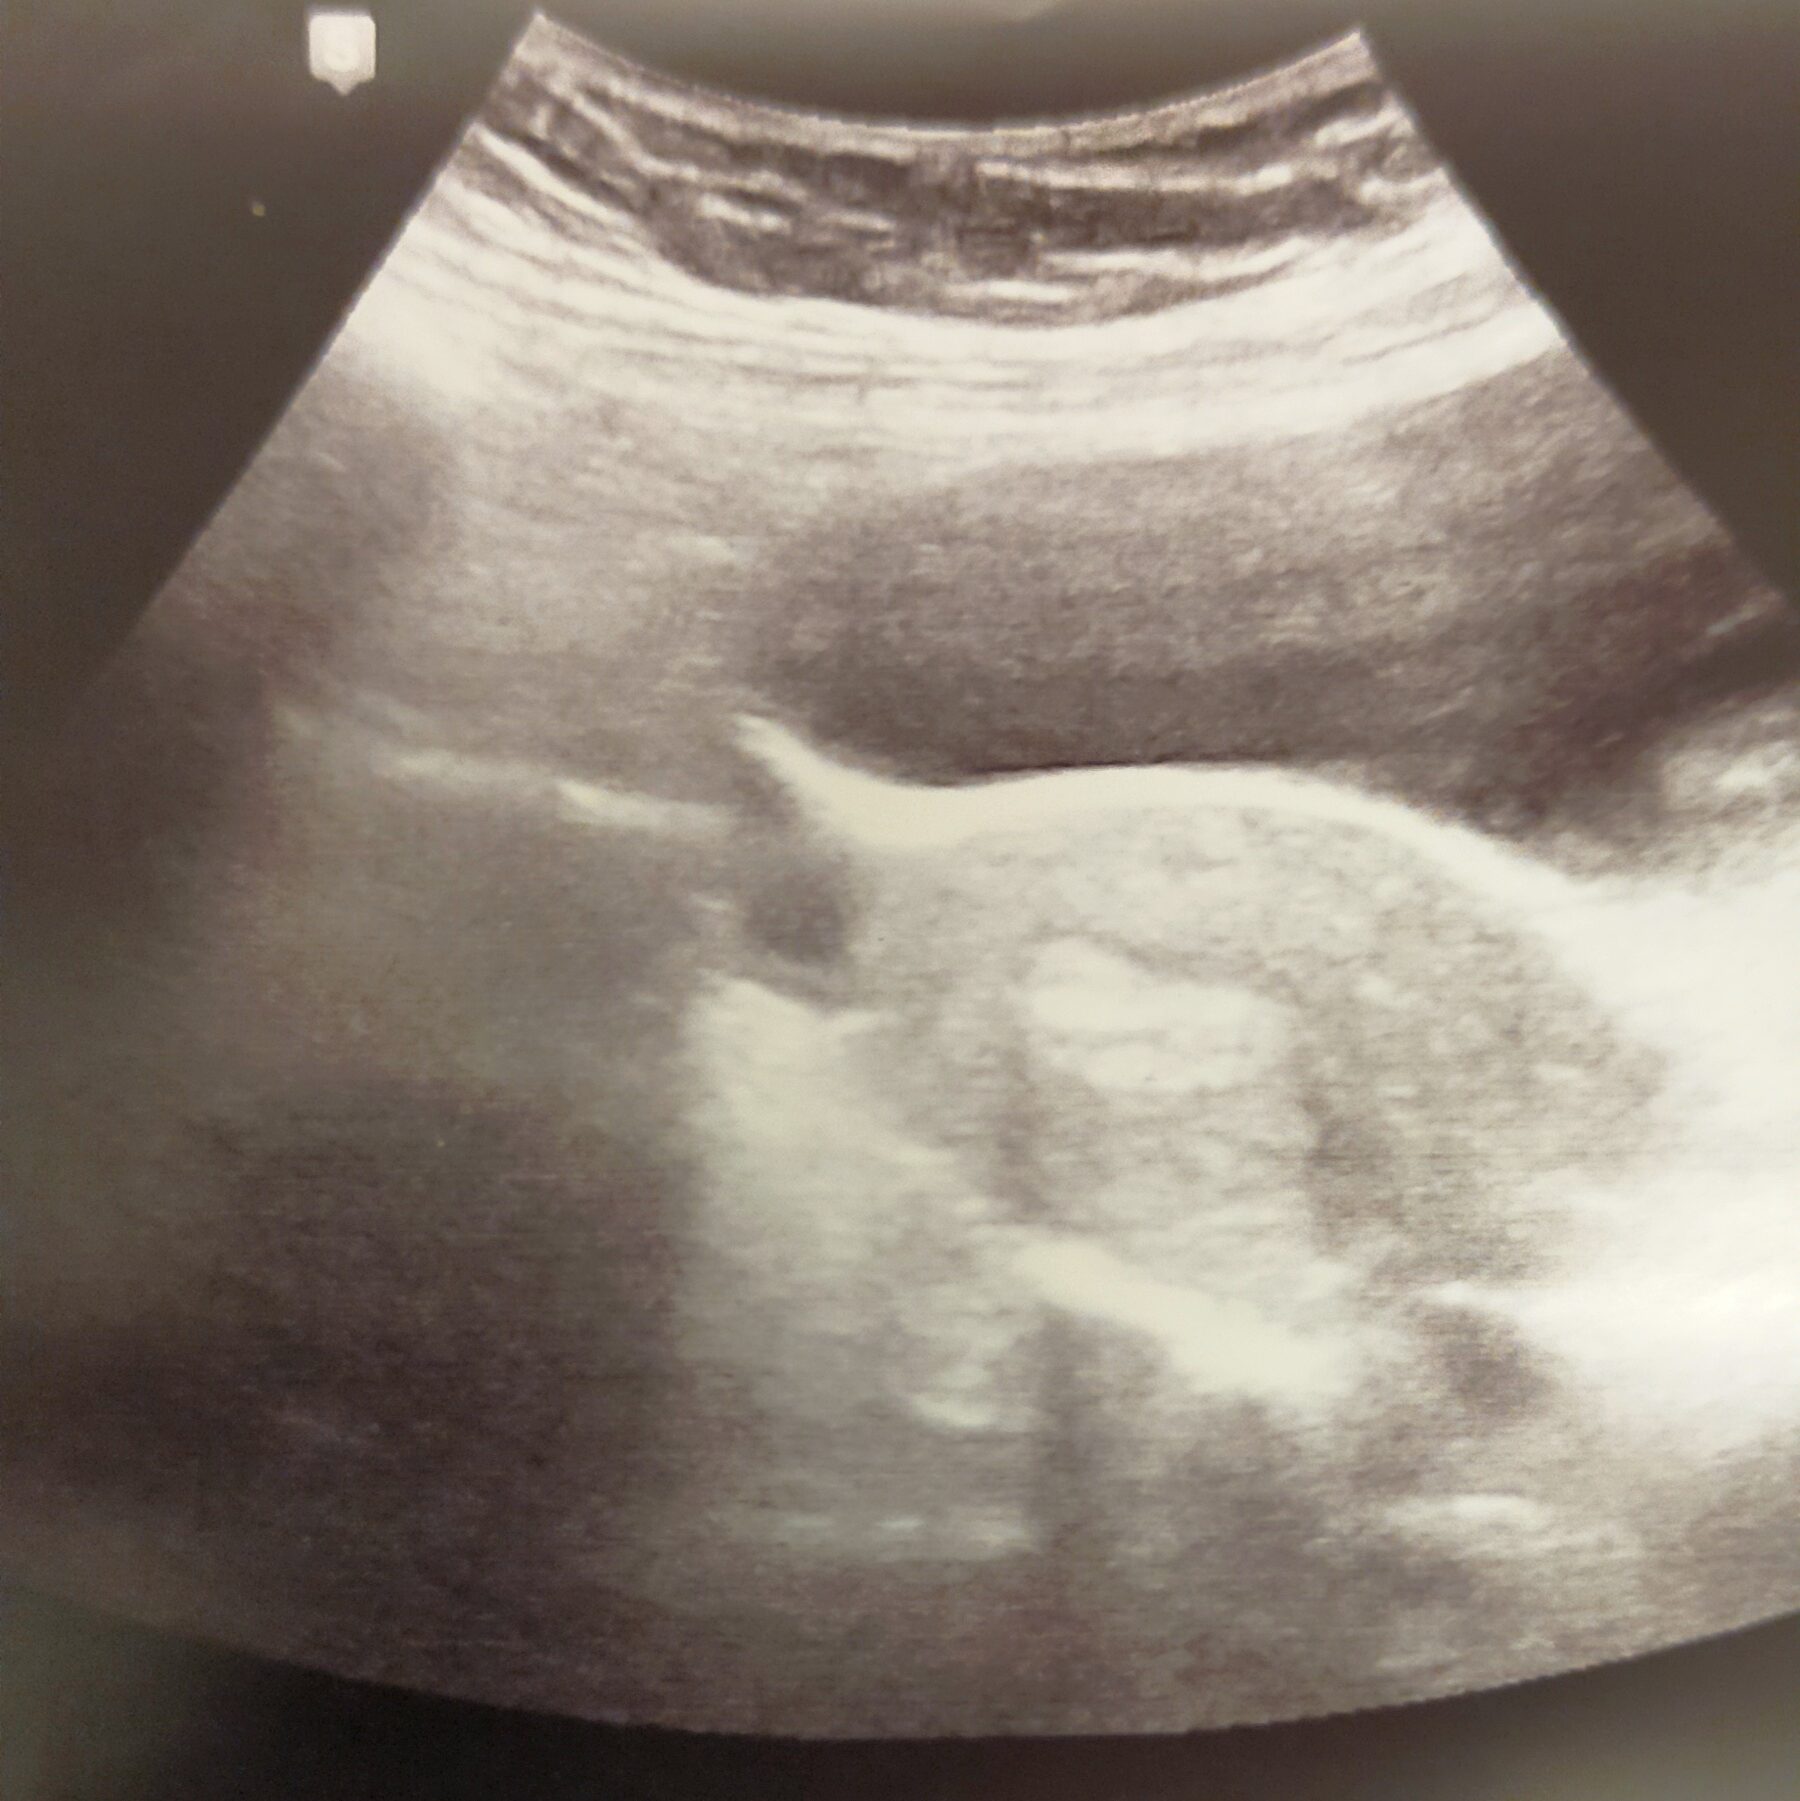

On redescend, et l’infirmier m’appelle immédiatement. J’enfile mes vêtements de lumière. Il vient me chercher. Je lui dis que je veux mon mari aussi. Il en parle au docteur, qui accepte. OUF ! Monsieur Loup enfile bonnet et blouse, et se faufile entre mon fauteuil et le mur. La docteur entre. Elle sera seule pour le transfert, alors que d’habitude il y a aussi une infirmière pour l’écho. Le laborantin derrière la vitre demande à la Doc si elle préfère se servir d’un « Wallas » ou d’un « Helios ». Elle choisit le second. Étant donné que ce mot grec veut dire « soleil », et que nous envisageons de donner le prénom qui en découle en 3ème prénom de notre fille, je prends aussi cela comme un signe.

Elle nous dit « j’ai de bonnes nouvelles pour vous », et j’entends « deux bonnes nouvelles ». On a deux embryons ? Ouiiii !!! Elle continue : « défiant toutes statistiques, vos trois ovocytes ont donné trois très beaux embryons. Nous allons donc transférer un très bel embryon, et les deux autres très beaux embryons sont vitrifiés. »

Je n’en reviens pas. Je suis à deux doigts de fondre en larmes, au lieu de quoi j’ai un ENORME sourire. Je check mon mari, je suis fière de nous, il garde ma main dans la sienne et le transfert se fait.